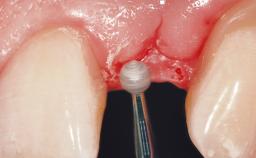

A 51-year-old female patient presented with a chief complaint of occlusal pain at tooth 24 and had been referred to our clinic for consultation and treatment. The patient had no history of any systemic disorder that may have affected the treatment outcome, and she was a non-smoker. Tooth 24 had been endodontically treated and restored with a crown at another clinic due to caries ten years before. The pre-treatment radiograph revealed a root fracture of tooth 24 with significant bone resorption. The pocket probing depth was 8 mm. The tooth had to be extracted. During the minimally traumatic extraction of tooth 24, a dehiscence was found on the buccal wall of the extraction socket. In response to the patient’s wish for a comprehensive treatment of the entire jaw,a suitable treatment plan was developed.